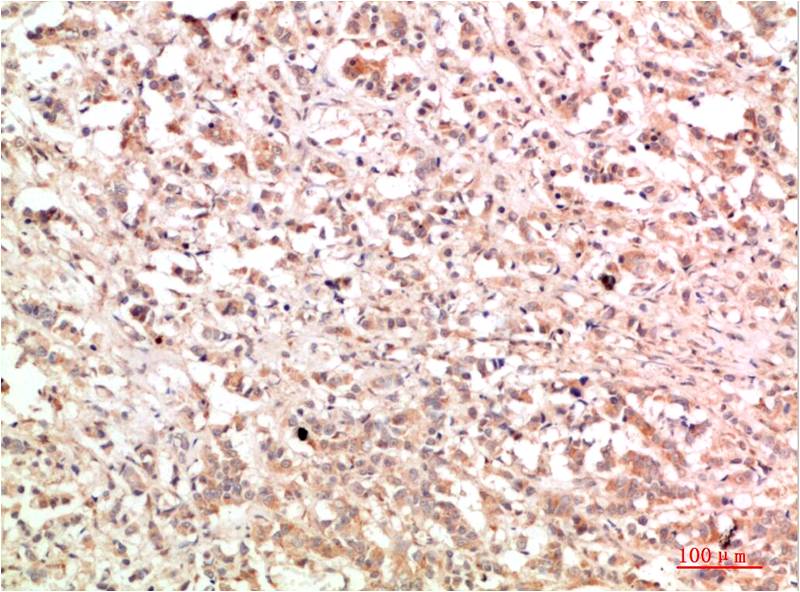

TTR Mouse Monoclonal Antibody(5G9)

Applications :WB, IHC

| Recommended dilutions: | WB 1:1,000-2,000 IHC 1:100-200 |

| Specificity: | The TTR Mouse Monoclonal Antibody can detects endogenous TTR proteins. |